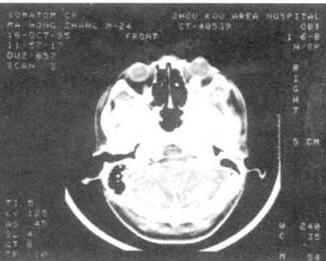

2.2 囊虫病猪的临床特征

猪囊尾蚴主要寄生于各部肌肉组织、舌肌、咬肌、心肌和其它器官组织中。动检人员必须按国家规定检疫程序操作,对每头屠猪必须进行严格检疫。

3.2 猪囊尾蚴的形态

成熟的猪囊尾蚴为长椭圆形,囊壁内充满液体,上有一个黍粒大小白色小结节即头节。未成熟囊尾蚴对人体健康具有潜在危害性。